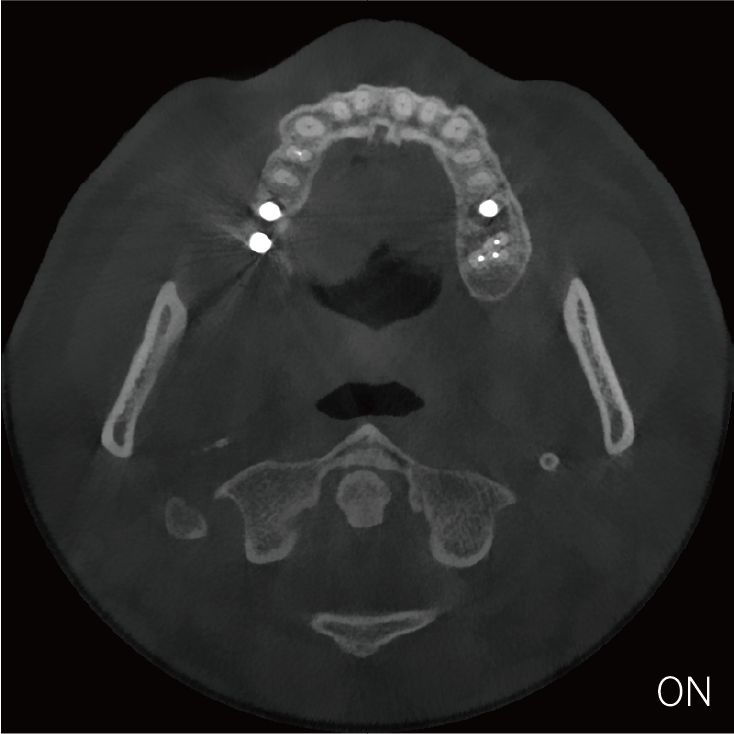

临床样片